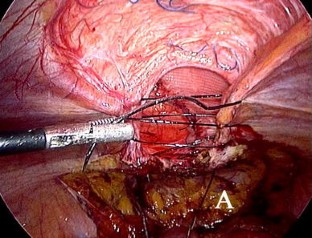

Fig. 2